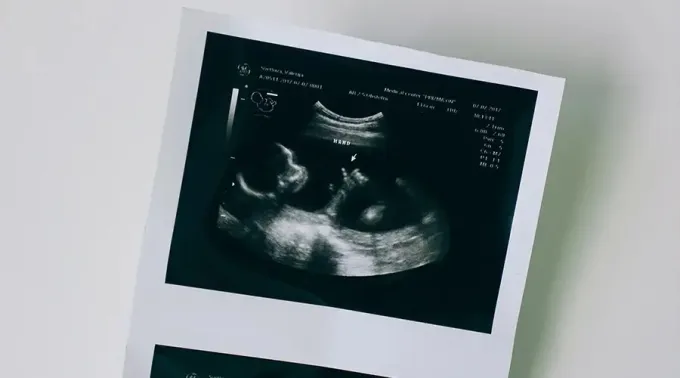

Entrou em vigor na Hungria uma lei que exige que os médicos façam as mães que querem abortar ouvir o som do batimento cardíaco do bebê antes de qualquer procedimento.

Com esta decisão, os médicos devem assinar um documento que comprova que as grávidas receberam "uma indicação claramente identificável dos sinais vitais do feto" antes de procederem a qualquer forma de aborto.

Ele também disse que equipamentos modernos podem detectar batimentos cardíacos no início da gravidez, o que pode fornecer "informações mais completas para mulheres grávidas".